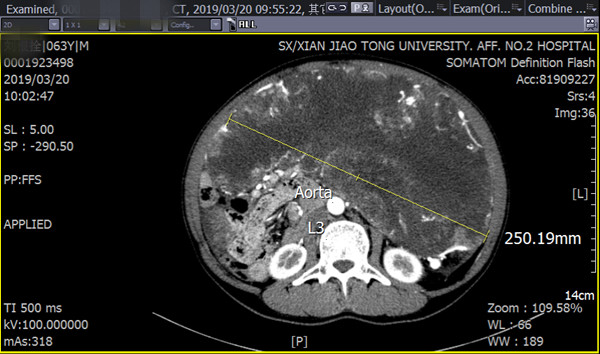

在完善术前检查过程中,发现该患者双肺多发肺大泡,经呼吸及危重症医学科会诊认为肺功能未提示全麻绝对禁忌,肺大泡存在术中破裂风险;下腹部CT平扫及增强扫描发现盆腹腔内巨大不规则囊实性肿块,部分边界欠清、临近腹腔结构受压移位、增强后病变呈明显不均匀强化,其内可见多发迂曲血管影;进一步CTA、CTV提示:主要由腹腔干、胃十二指肠动脉分支供血,经粗大引流静脉汇入脾静脉。为制定安全有效的手术方案,普外科专家组进行多次术前评估,并组织多学科MDT讨论,同时向医务部报备重大手术计划。